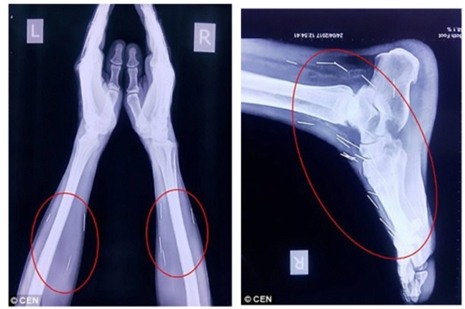

Daily Mail đưa tin, ông Badrilal Meena (56 tuổi) đến từ TP Kota, bang Rajasthan, miền Bắc Ấn Độ được đưa vào bệnh viện để phẫu thuật ngón chân cái thì bác sĩ phát hiện trong chân ông có nhiều cây kim. Sau khi tiếp tục kiểm tra, các bác sĩ phát hiện có tới 75 cây kim trong cơ thể ông Meena. Trong số 75 cây kim, có 40 cây nằm trong cổ họng, 25 cây ở chân và 2 cây ở cánh tay.

Chân và tay bệnh nhân cũng có hàng chục cây kim khác. Ảnh: DAILY MAIL |